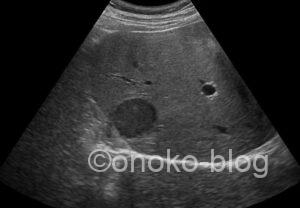

腹痛で来院された男性。

腸管かな~なにかあるかな~と思いながらプローブをあてると

おおっと(゚д゚)!

立派な充実性腫瘤ですね。測ると90㎜程ありました。

門脈も圧排されているように見えますよね。

腫瘤の内部エコーはカラードプラによる血流シグナルは認めず、

かつゼリーのようにふるふると動くのが確認できました。

最近発熱はなかったとの事でしたが、エコー所見から

肝膿瘍の疑いで報告書を提出し、他院紹介。

精査の結果アメーバ性肝膿瘍の診断とのお返事をいただきました。

アメーバ性肝膿瘍は単発で、右葉に多いそうです。

病期によってエコー所見が違うのも特徴ですよね。

(過去の症例もアメーバ性肝膿瘍でした)